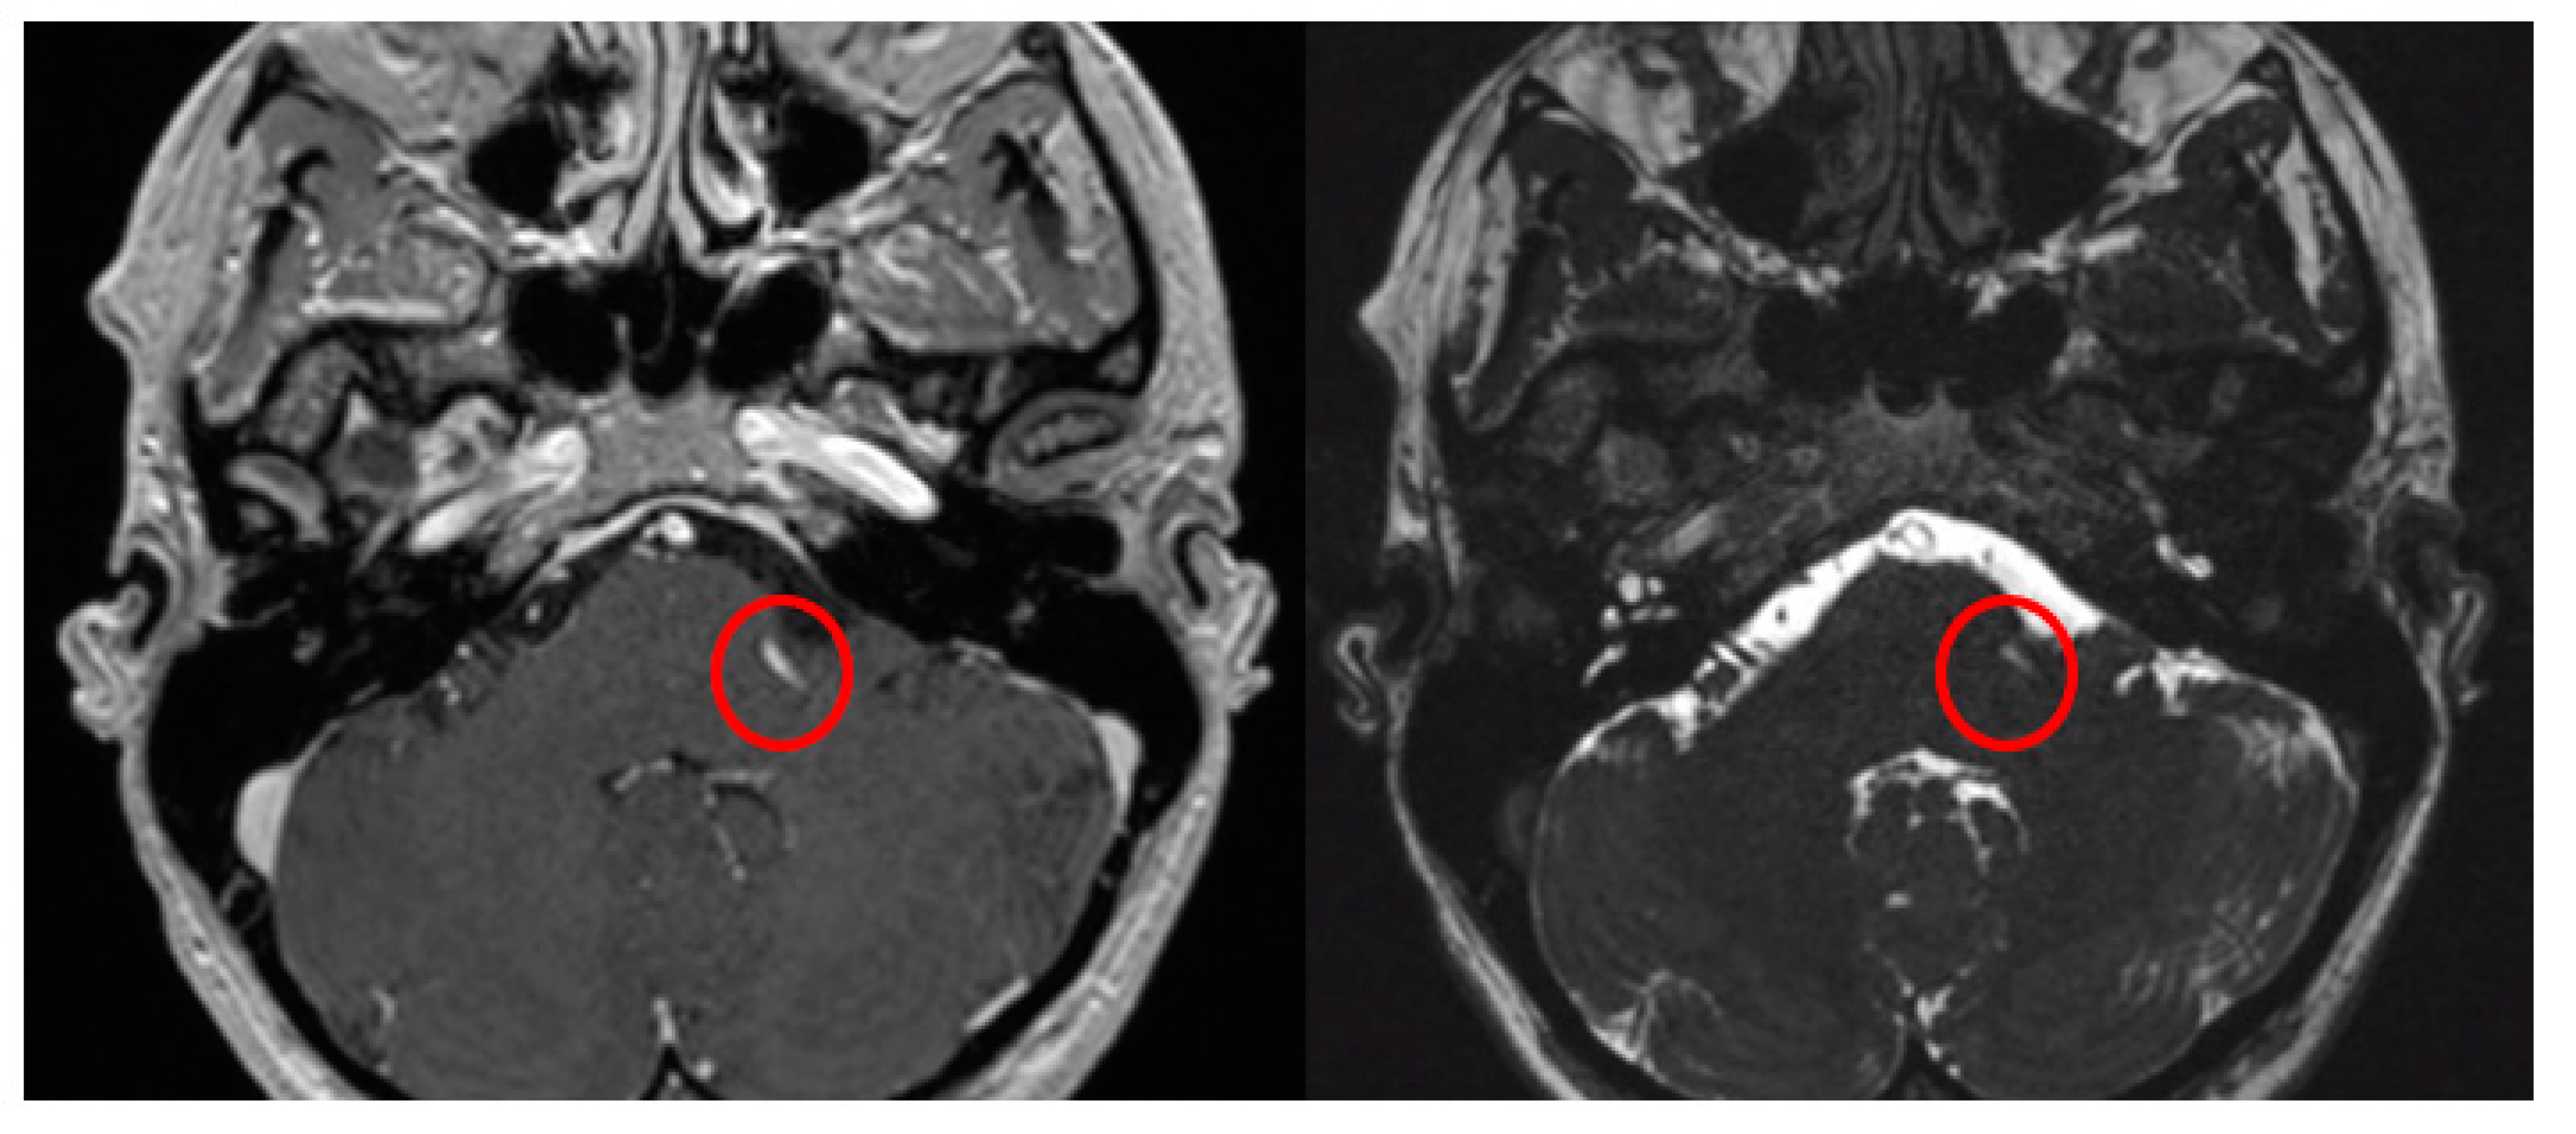

When the trajectory of the vessel is evaluated in the coronal view, it may be possible to visualize the vessel forming a loop superior and medial (towards the exit of the facial nerve) (Figure 1). When the MRI is visualized in the axial view, at the highest level of the loop in the coronal section, the proximity of the vascular structures to the pons may be seen in the axial view as if the artery was located inside of the brainstem, surrounded by the pons parenchyma (Figure 2).

Figure 1.

The axial view gives the false impression that the artery is located inside the pons (A). However, the coronal view clearly demonstrates that the vessel does not enter the brainstem (B). The yellow arrows point to the local of the NVC.